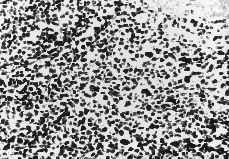

La anatomía patológica diagnostica linfoma no Hodgkin T periférico inespecífico que afecta de manera difusa a útero y a cérvix (Figs. 1 y 2). La biopsia de mama añade linfoma no Hodgkin de alto grado de tipo T con células que exhiben una mayor desdiferenciación que en la biopsia del útero (Fig. 3).

Figura 3.Proliferación linfoide maligna de mama con patrón difuso (H.E.).